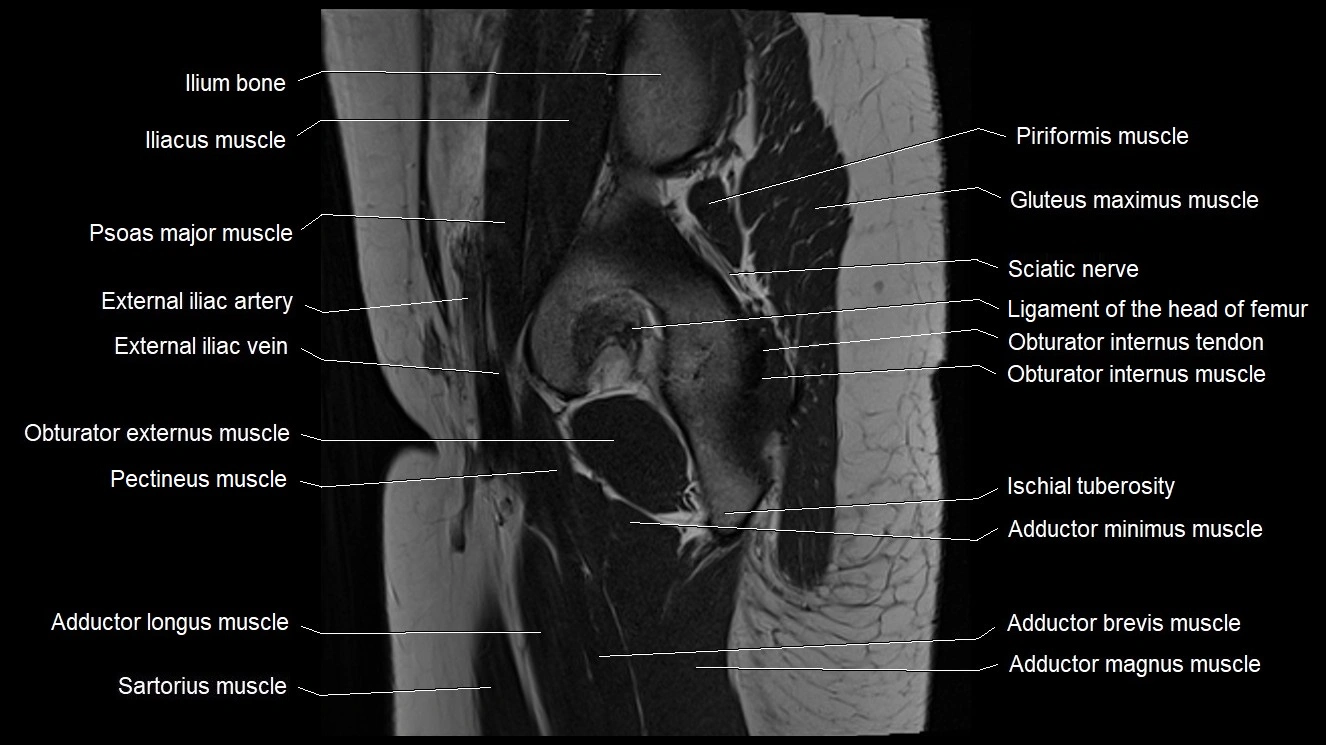

- Acetabulum

- Adductor brevis muscle

- Adductor longus muscle

- Adductor magnus muscle

- Adductor minimus muscle

- Gluteus maximus muscle

- Gluteus medius muscle

- Gracilis muscle

- Ischial tuberosity

- Ligamentum teres (ligament of the head of femur)

- Obturator externus muscle

- Obturator internus muscle

- Obturator internus tendon

- Pectineus muscle

- Psoas major muscle

- Sacral plexus

- Sartorius muscle